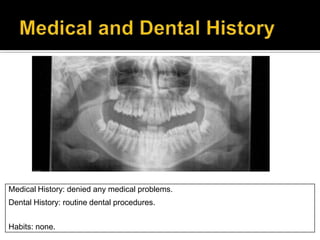

Medical History: denied any medical problems.

All teeth are present

Impacted upper and lower 8’s.